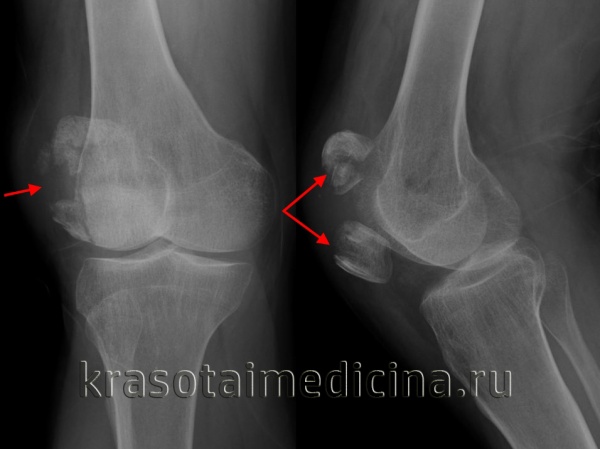

1. Надколенник, состоящий из двух и более частей:

• Вторичный центр(ы) окостенения обычно в области верхнебоковой поверхности надколенника

• Гладкие края при рентгенографии

• Костные осколки не целостные, а лежащий сверху хрящ гладкий

• У 2-8% людей (симптомы только у 2% пациентов)

• М:Ж = 9:1

• В 40-45% случаев двусторонний: необходимо учесть данные рентгенографии другого коленного сустава

Какие заболевания имеют симптомы, схожие с переломом надколенника

Двойной или множественный надколенник

- Типичное расположение верхнебоковой части надколенника

- Костные фрагменты (два или множественные) не могут быть сопоставлены вместе (в отличие от перелома)